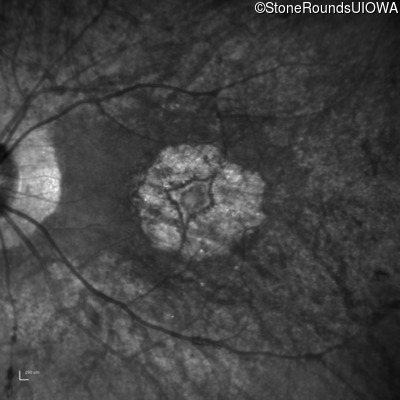

Blue Autofluorescence - Right - 20/25

Exemplar